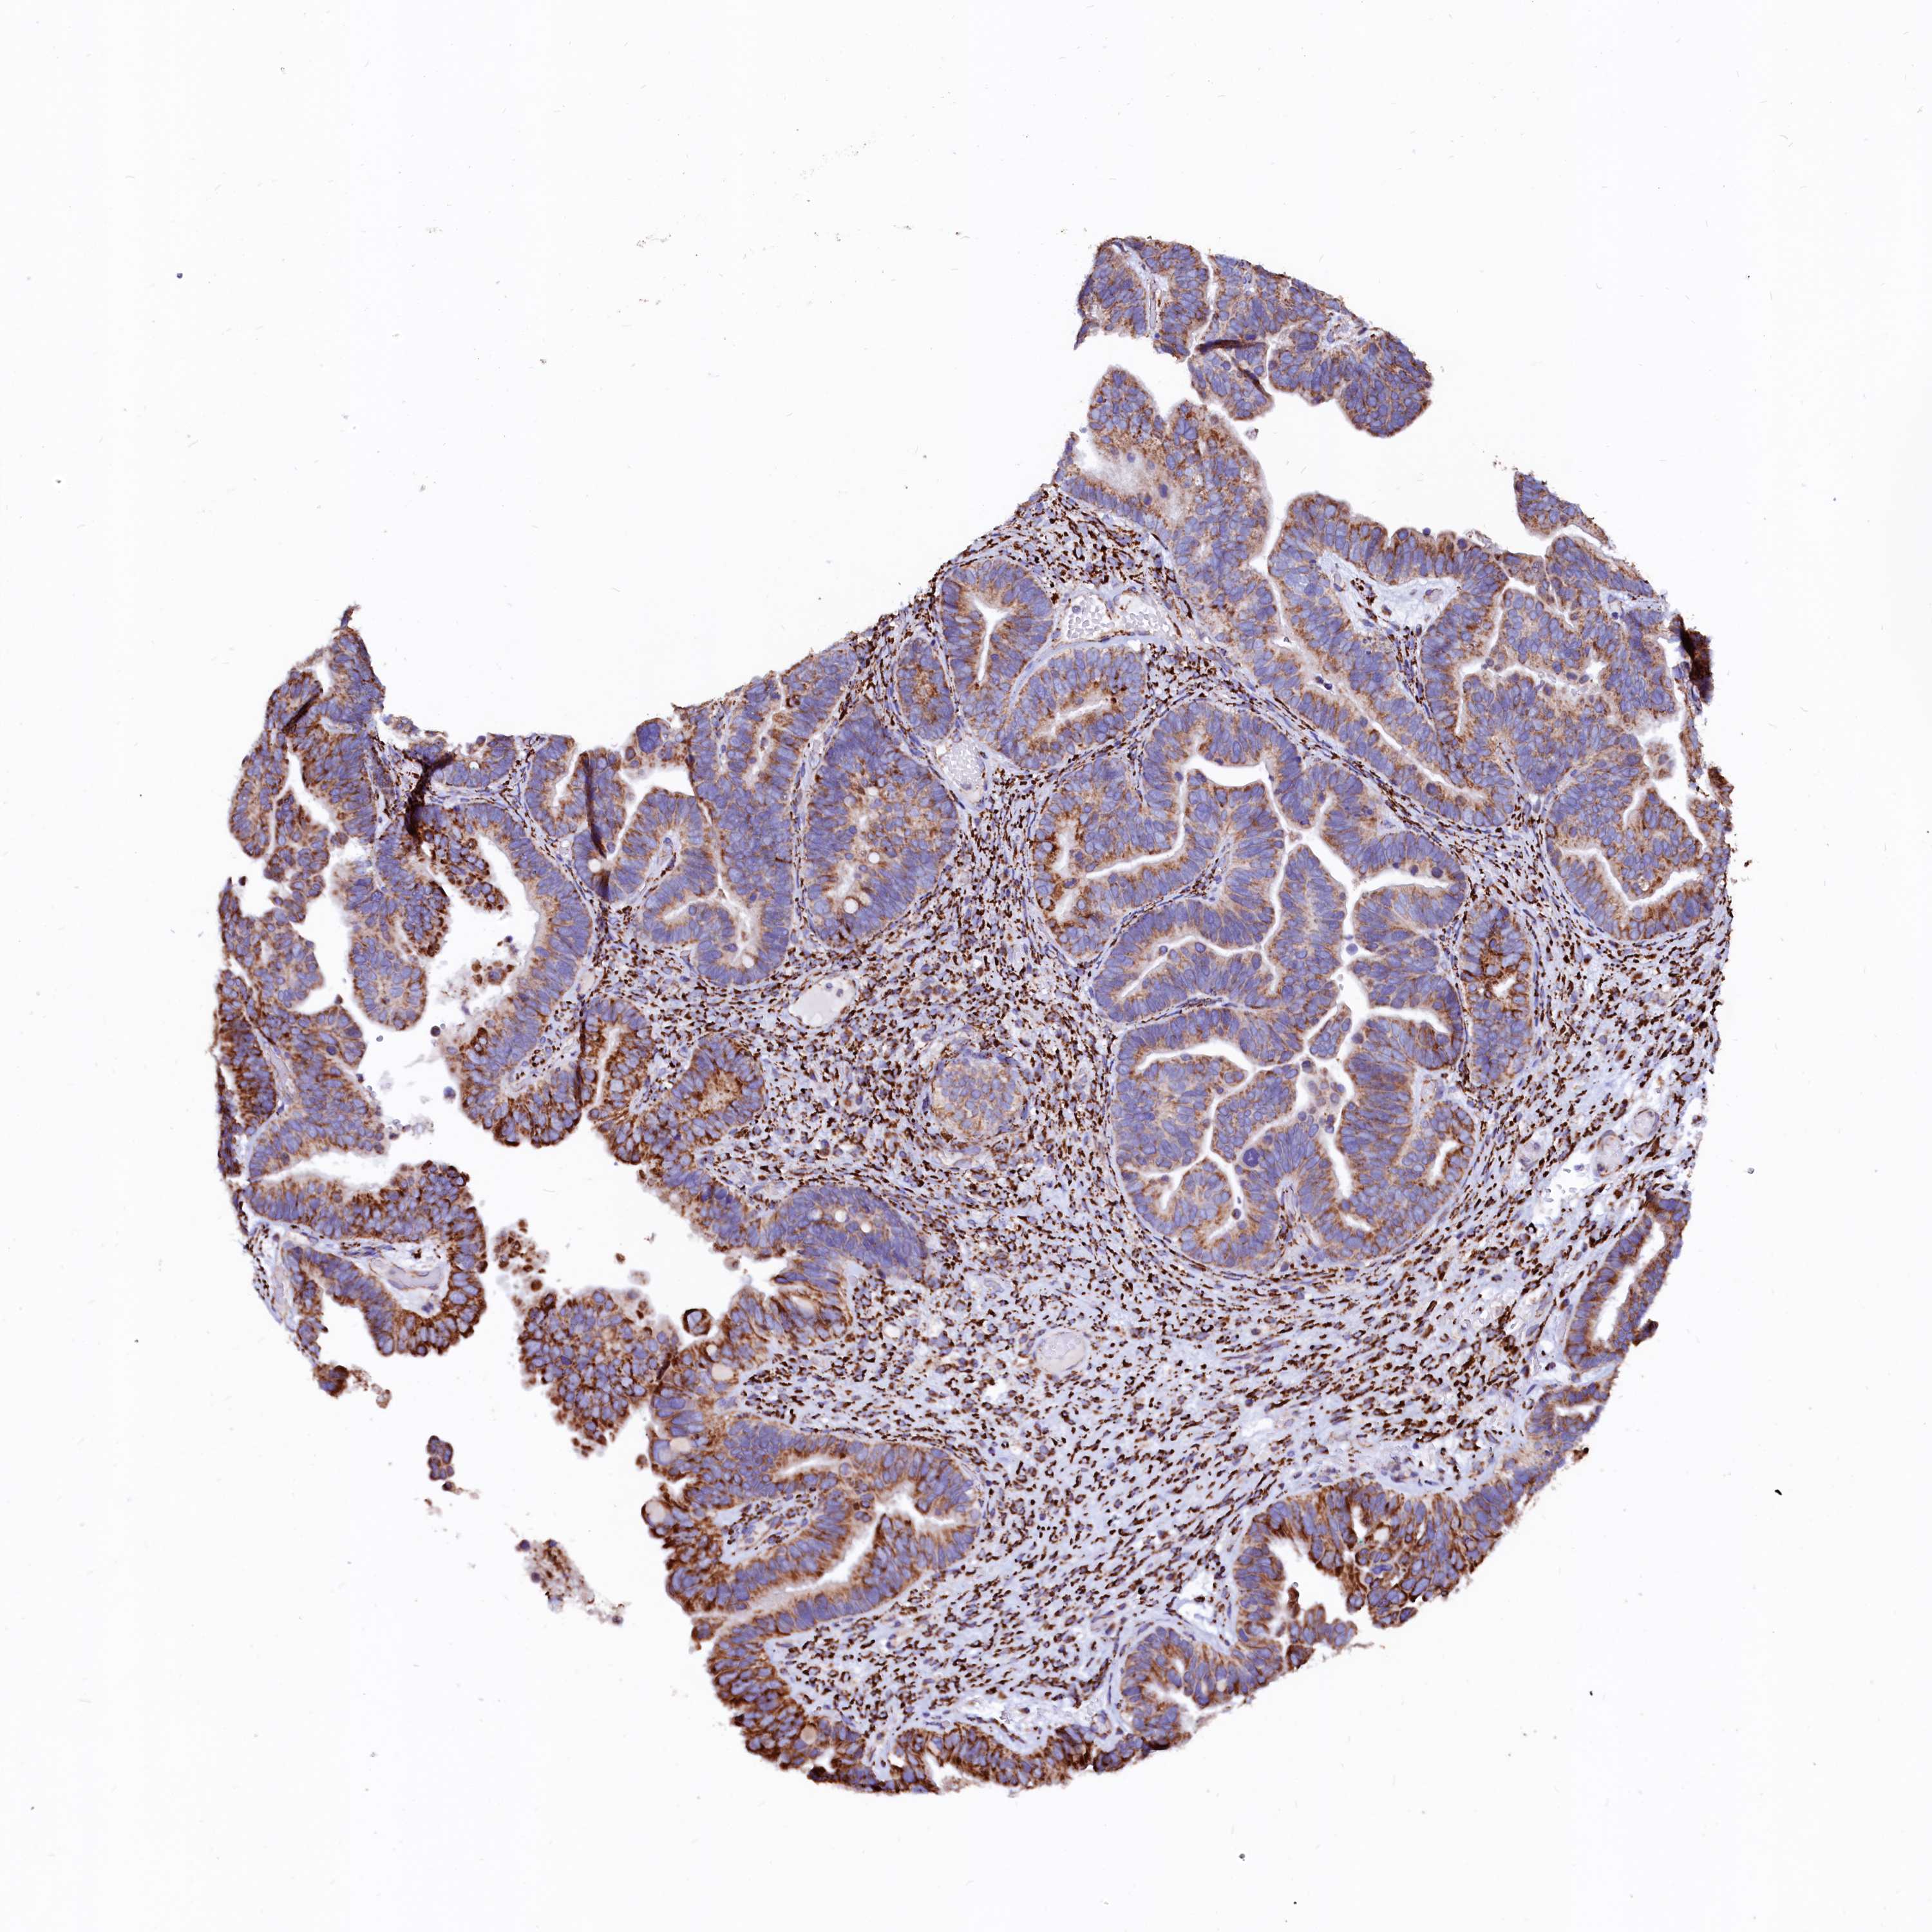

OVARIAN CANCER - Protein expressioni

A mouse-over function shows sample information and annotation data. Click on an image to view it in a full screen mode. Samples can be filtered based on level of antibody staining by selecting one or several of the following categories: high, medium, low and not detected. The assay and annotation is described here.

Note that samples used for immunohistochemistry by the Human Protein Atlas do not correspond to samples in the TCGA dataset.

Antibody stainingi

Antibody staining in the annotated cell types in the current human tissue is reported as not detected, low, medium, or high, based on conventional immunohistochemistry profiling in selected tissues. This score is based on the combination of the staining intensity and fraction of stained cells.

Each image is clickable and will lead to virtual microscopy that enables deeper exploration of all samples and also displays staining intensity scores, fraction scores and subcellular localization as well as patient and tissue information for each sample.

Antibody HPA002328

Antibody CAB037200

Staining

High

Medium

Low

Not detected

Intensity

Strong

Moderate

Weak

Negative

Quantity

>75%

75%-25%

<25%

None

Location

Nuclear

Cytoplasmic/membranous

Cytoplasmic/membranous,nuclear

Cystadenocarcinoma, mucinous, NOS

Carcinoma, endometroid

Cystadenocarcinoma, serous, NOS

Carcinoma, NOS